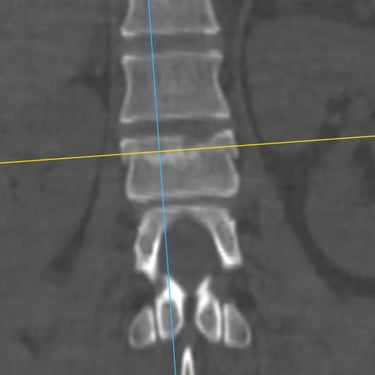

Fractura Vertebral Lumbar: Estabilización Segura con Fijación Transpedicular (FTP)

La fractura vertebral lumbar es una lesión que puede comprometer la estabilidad de la columna y las estructuras neurológicas. En casos seleccionados, el tratamiento quirúrgico mediante artrodesis con fijación transpedicular (FTP) ofrece una estabilización sólida de los segmentos afectados, restaurando la alineación vertebral y permitiendo una movilización temprana. Esta técnica reduce el dolor, previene deformidades progresivas y protege las raíces nerviosas. La intervención oportuna, acompañada de una adecuada rehabilitación, contribuye a una recuperación funcional segura y a una mejora significativa en la calidad de vida del paciente.